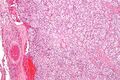

Carotid body tumour 2 intermed mag.jpg

صورة مجهرية لـ "جسم الشريان السباتي ورم" (نوع من ورم المستقتمات).

صورة مجهرية لورم في الجسم السباتي مع الزيلبالين المميزة . صبغة الهيماتوكسيلين واليوزين .

تظهر أورام المستقتمات بشكل كبير على شكل كتل سليلة الشكل متحددة بشدة ولديها اتساق مطاطي متماسك. وهي أورام وعائية شديدة وقد يكون لها لون أحمر غامق.[بحاجة لمصدر]

عند الفحص المجهري ، يتم التعرف على الخلايا السرطانية بسهولة. الخلايا السرطانية الفردية هي متعددة الأضلاع إلى بيضاوية ويتم ترتيبها في كرات خلوية مميزة تسمى زيلبالين.[7] يتم فصل كرات الخلايا هذه بواسطة سدى ليفي وعائي وتحيط بها الخلايا المعلقة .